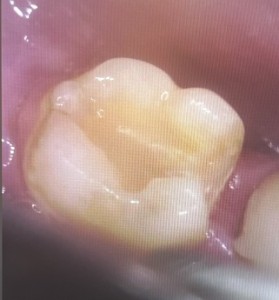

6日目 セラミックの被せ物と詰め物を装着しました。

これまで患者様は、治療に対する要望や不安を歯科医師になかなか相談できず、お口の中の状態がよくわからなかったそうです。今回、口腔内カメラで撮影しながら治療の過程を英語で説明していきました。大きな画面ではっきりと見やすく、説明を聞いて納得しながら治療を受けられたことが嬉しいとおっしゃっていました。